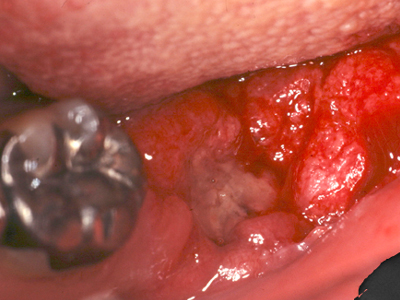

さらにその3w後。浮腫性の歯肉が乾いた感じに変化しました。歯肉が治ろうとするサインです!この時を見逃さず、ポケット底から縁上まで1歯につき1回でルートプレーニングをします。

1ヶ月後、プロービングデプスは2〜3mmに改善しました。